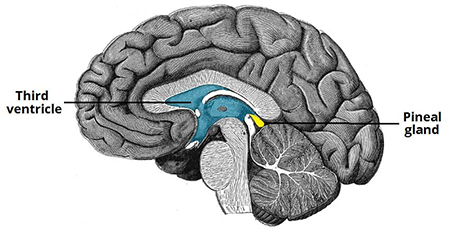

آناتومی و عملکرد غده صنوبری

غده صنوبری به شکل مخروط کاج است و به اندازه یک نخود است و قطر آن تقریباً 8 میلی متر است. در اپیتالاموس، ناحیه ای از مغز که بین دو نیمکره قرار دارد و توسط تالاموس احاطه شده است، قرار دارد. غده صنوبری از پینهآلوسیتها تشکیل شده است که سلولهای تخصصی هستند که ملاتونین، هورمونی که چرخه خواب و بیداری را تنظیم میکند، تولید و ترشح میکنند.

تولید ملاتونین توسط بخشی از مغز به نام هسته سوپراکیاسماتیک (SCN) که در هیپوتالاموس قرار دارد، کنترل می شود. SCN اطلاعات مربوط به چرخه های نور و تاریکی را از چشم دریافت می کند و سیگنال هایی را برای تنظیم تولید ملاتونین به غده صنوبری ارسال می کند. در طول روز، زمانی که نور بیشتری وجود دارد، SCN سیگنال هایی را برای سرکوب تولید ملاتونین ارسال می کند. در شب، زمانی که نور کمتری وجود دارد، SCN سیگنال هایی را برای تحریک تولید ملاتونین ارسال می کند که به بهبود خواب کمک می کند.